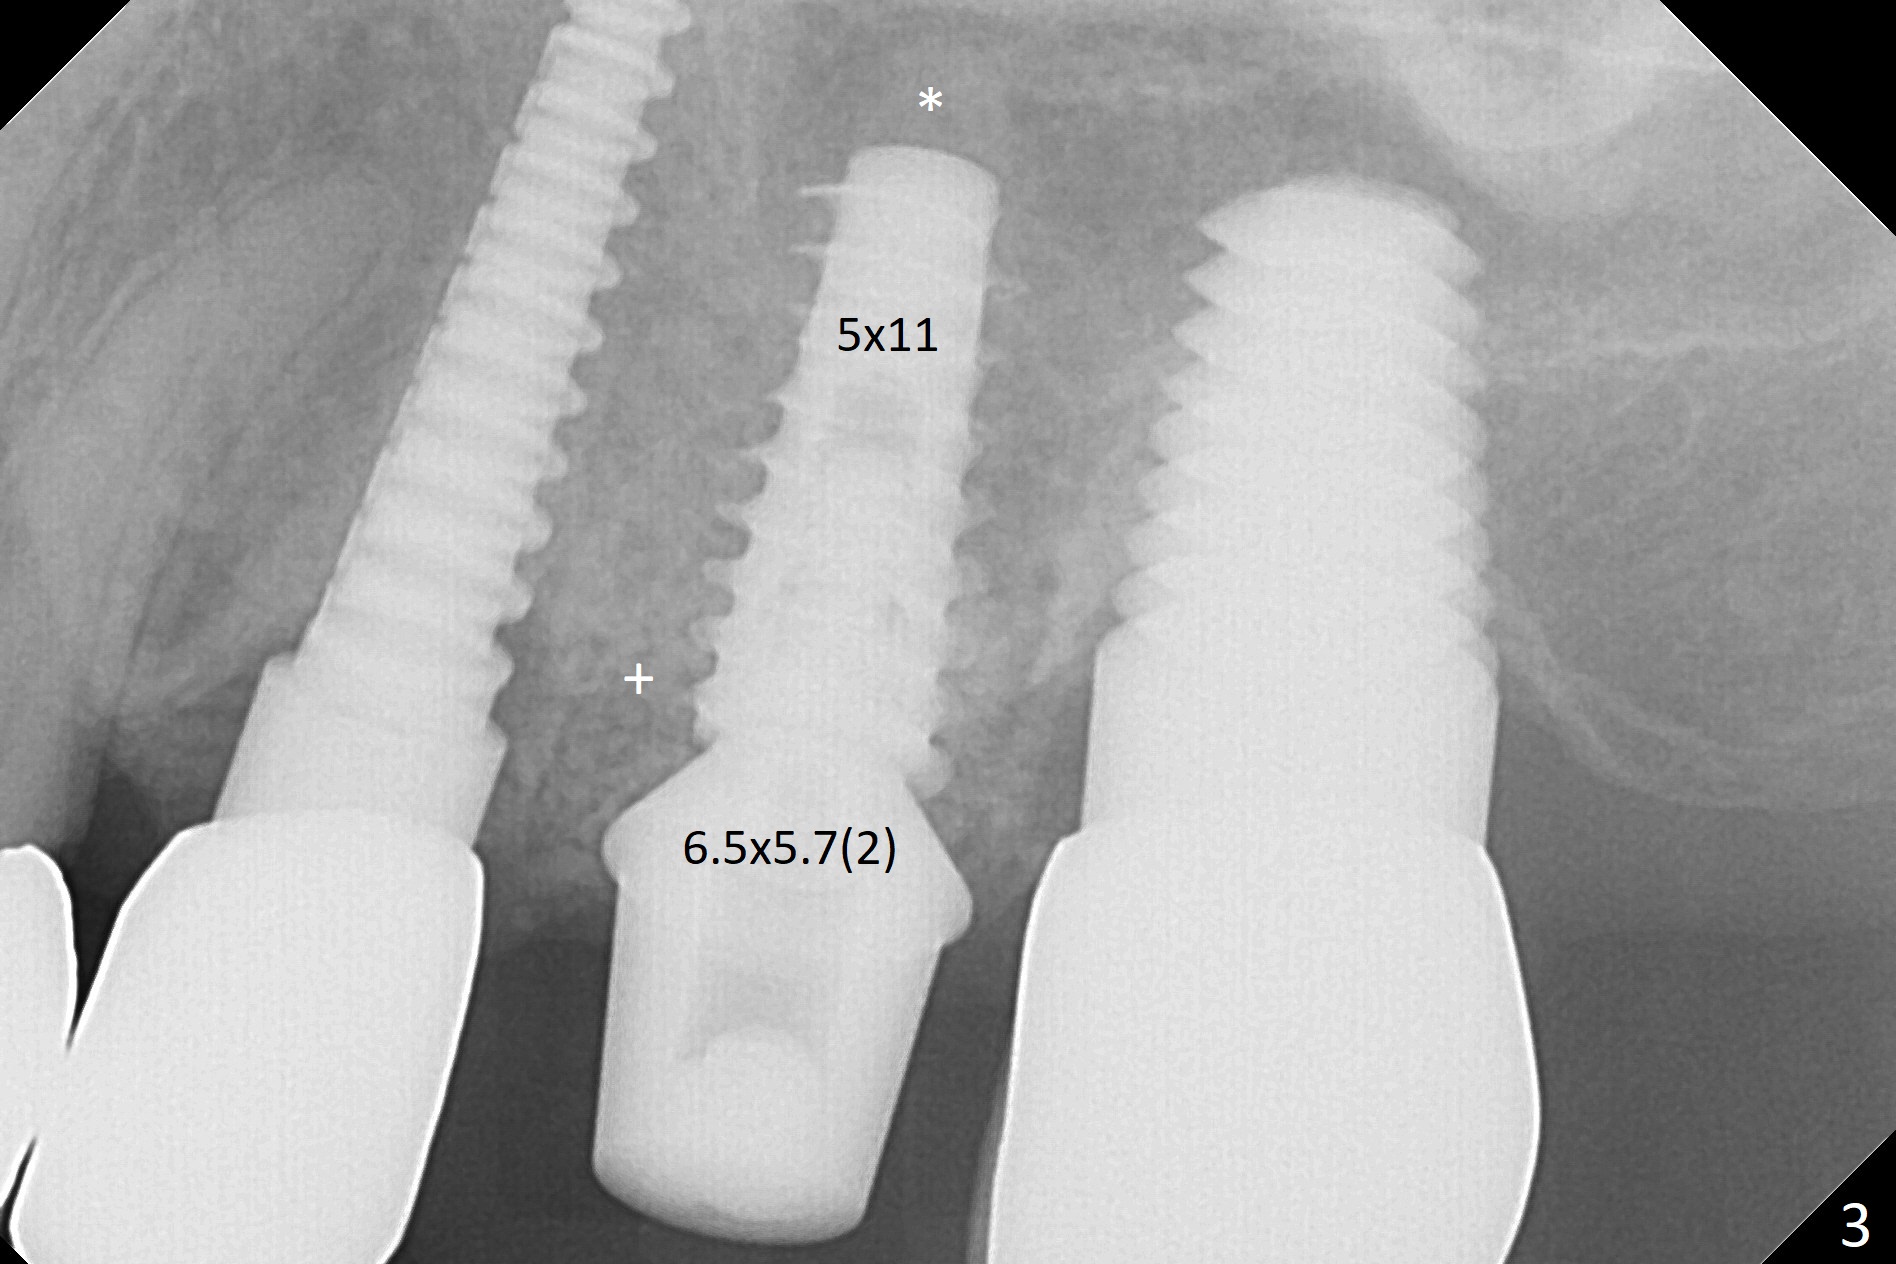

Initial osteotomy in the septum of the tooth #14 is 9 mm, approximately 2 mm from the sinus floor (Fig.1).  Subsequent osteotomy depth is 11 mm, followed by insertion of a 4.5x11 mm dummy implant (Fig.2).  After use of Magic Drill (MD) 4.8 mm for 9 mm, a 5x11 mm IBS implant is placed with sinus lift without additional bone graft (Fig.3 *).  In contrast, autogenous bone (from MD) and Vanilla Graft are meticulously placed in the remaining socket (+) before and after placement of a 6.5x5.7(2) mm abutment.  An immediate provisional is fabricated to close the sockets.  There is buccal tenderness 1-3 months postop.  There is distopalatal implant thread exposure.  A healing abutment (5.5x2 mm) is placed.  CT confirms thin buccal plate (Fig.4,5).  It appears that the implant should have been as palatal as possible.  The tenderness remains for the next 2 weeks.  When the healing abutment is removed, the implant seems to have been placed shallow, ~ 1 mm subgingival (Fig.6).  With local anesthesia, the implant is reversed to clean the coronal threads with Titanium brush and copious irrigation (Fig.7).  The implant is then placed ~4 mm subgingival (Fig.8) and slightly subcrestal (Fig.9,10).  It appears that the postop bone loss (Fig.9 *, as compared Fig.1,2) makes the implant look to be placed too shallow.  When the implant is being placed deeper, the buccal plate feels intact.  The early periimplantitis is apparently due to postop bone loss more than buccal placement, although certain degree of buccal bone resorption must occur.  A 6x4 mm healing abutment is placed.  Left facial swelling develops 2 days post implant elevation (Fig.11,12, as compared to preop (Fig.13)).  The left maxillary sinus cloud (Fig.12) appears to be a false positive finding, since the same feature exists prior to implant elevation (Fig.13).  Both sinuses look clear prior to implant elevation (Fig.14).  Amoxicillin switches to Augmentin and Flagyl, since the patient is reluctant to have the implant removed.  Finally the sinus infection is under control.  The patient feels left facial swelling 9 months postop (5 months post elevation) and reports left nasal discharge ~ 1 month earlier.  There is mild buccal plate tenderness.  The implant seems to be buccally placed (Fig.15,16), although there is no significant change radiographically (Fig.17).  The implant is removed with bone graft (Fig.18 *).  To avoid complication and failure, an immediate implant at the upper 1st molar should be short and placed deep.